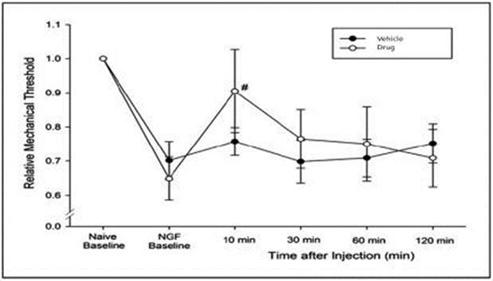

In addition to relief of symptoms, inflammation, pain, and others, we believe INM-755 may impact the underlying disease by enhancing skin integrity in a subset of EB patients. We have completed more than 30 preclinical pharmacology and toxicology studies to investigate the effects of CBN. Several of these nonclinical studies explored the effect on important symptoms such as pain and inflammation. In in vitro pharmacology studies, CBN demonstrated activity in reducing markers of inflammation. CBN upregulated expression of a type of keratin called keratin 15, or “K15”, which might lead to skin strengthening and reduced blister formation in EB simplex, or “EBS”, patients with mutations in another keratin called keratin 14, or “K14”. The anti-inflammatory activity of CBN may be beneficial in healing chronic wounds caused by prolonged inflammation. Following a review of our toxicology studies, the Netherlands National Competent Authority and Ethics Committee approved the initiation of a Phase I clinical study in healthy volunteers. We have safety data with INM-755 cream in 22 healthy adult volunteers from our first Phase I study (755-101-HV) in which subjects had the INM-755 cream applied to their upper backs daily for 14 days. An interim safety analysis of the first 16 subjects was reviewed by the Netherlands National Competent Authority and Ethics Committee and determined to be adequate to allow initiation of the second Phase I study testing INM-755 cream on small wounds. That second study has completed and we now have safety data for INM-755 cream applied to small open wounds daily for 14 days in 8 healthy adult volunteers.

CBN is also the active ingredient in our second drug candidate, INM-088, which is in preclinical studies as a potential treatment for glaucoma. We are conducting studies to test INM-088’s ability to provide neuroprotection and reduce intraocular pressure in the eye. We compared several cannabinoids, including CBD and THC, to determine which cannabinoid was the best drug candidate for the treatment of glaucoma. Of all the cannabinoids examined in preclinical studies, CBN demonstrated the most optimal neuroprotection effect. Furthermore, CBN also exhibited intraocular pressure reduction capability. INM-088 is in advanced formulation development.

Current treatments for glaucoma primarily focus on decreasing fluid build-up in the eye. Our data has shown that INM-088 may provide neuroprotection in addition to modulating intraocular pressure by improving drainage of fluid in the eye. Thus far, we have conducted numerous preclinical pharmacology studies to demonstrate these effects.